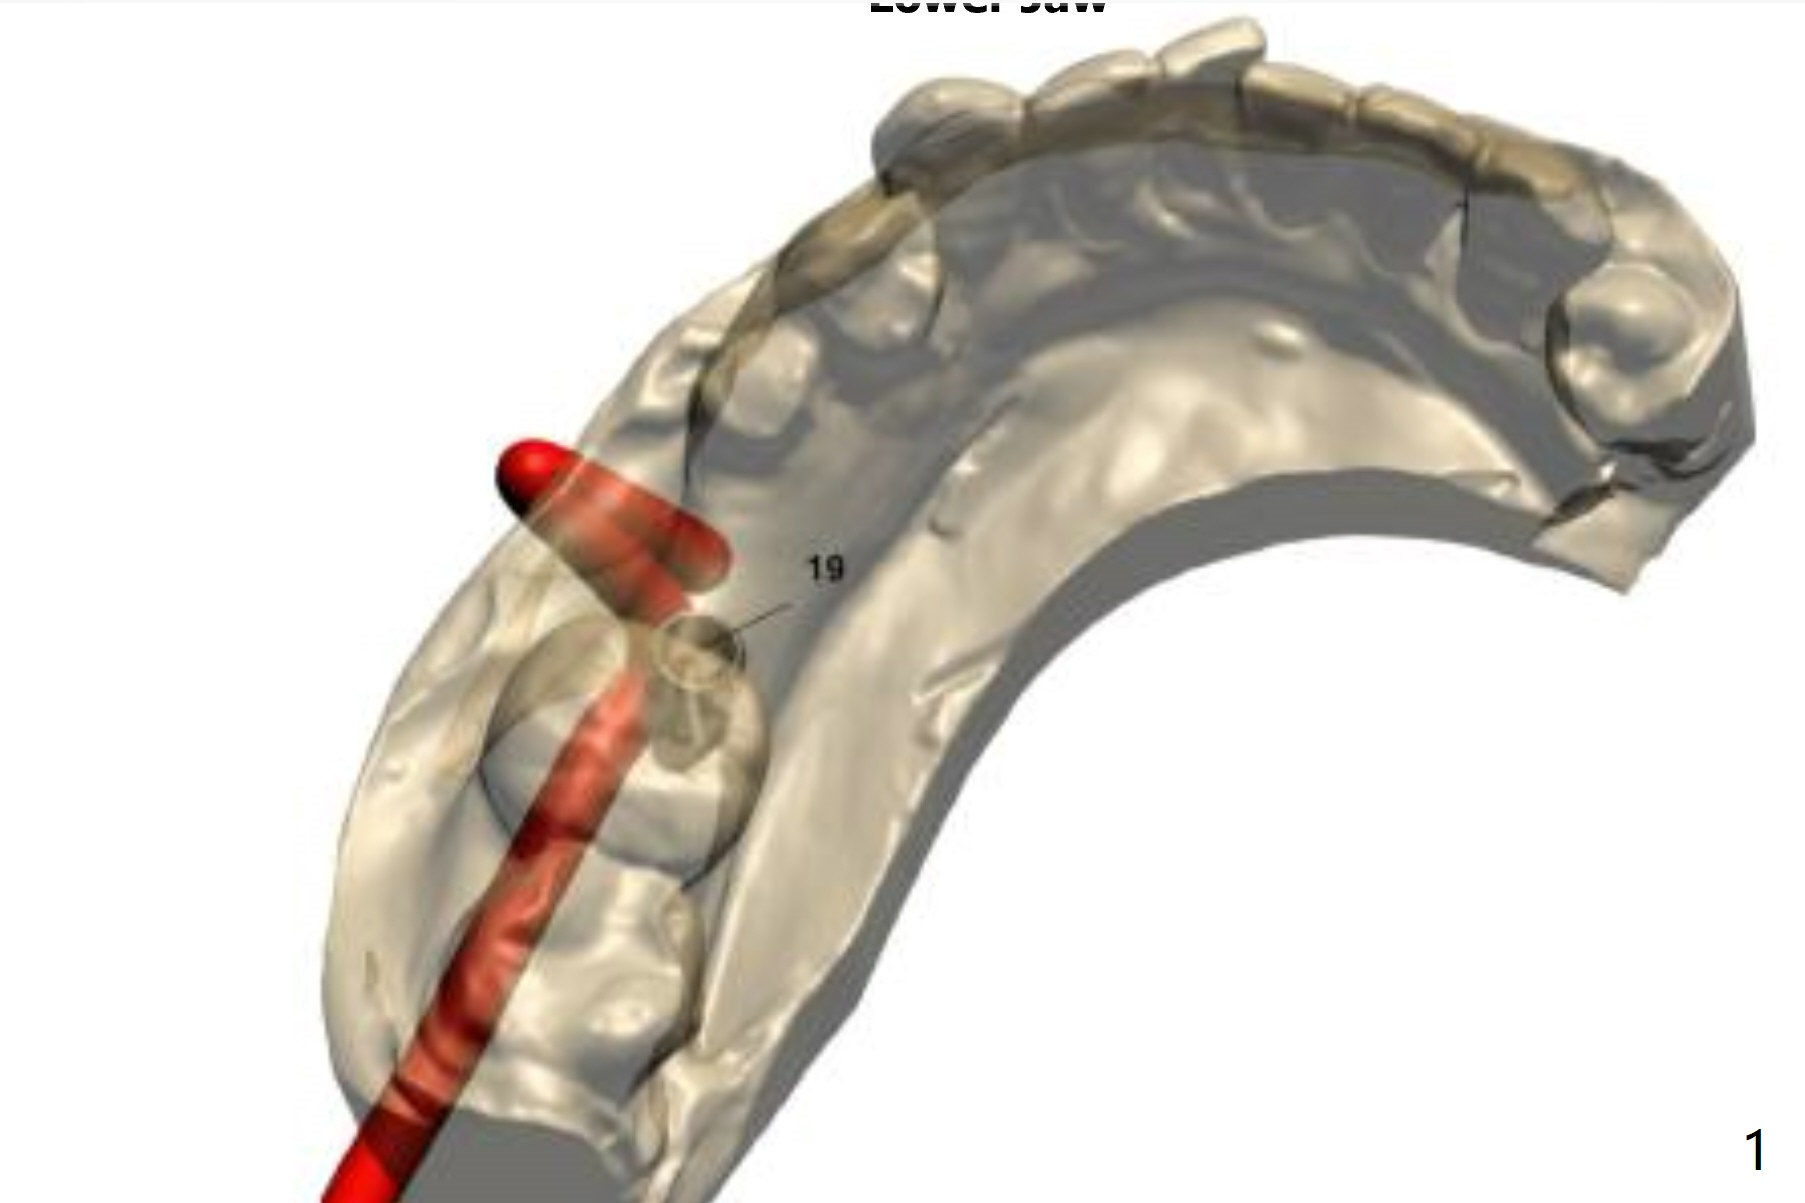

4 mm Implant for Molar

Return to Lower Molar Immediate Implant, Trajectory